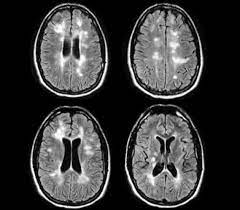

يكشف الرنين المغناطيسي عن مناطق مرض التصلب العصبي المتعدد في الدماغ والحبل الشوكي. كيف يهاجم التصلب اللويحي المتعدد ؟ في الاشخاص المصابين بالمرض , يهاجم الجهاز كيف يُشخص التصلب اللويحي المتعدد ؟ تجرى عادة الفحوصات بالاضافة الى اخذ التاريخ اكثر من 90% من المصابين بالمرض يوجد لديهم ندبات تظهر من خلال اشعة الرنين المغناطيسي ( mri. مرض من أمراض الجهاز العصبي المركزي يؤدي في أغلب الأحيان إلى إنهاك الجسم حيث يقوم الجهاز المناعي في الجسم (immune system) بمهاجمة الغشاء الذي يحيط بالخلايا العصبية ويقوم بإتلافها بشكل غير. يساعد العلاج الطبيعي في تخفيف مشاكل وهن وتيبس العضلات وتقلصها ومشاكل الحركة، حيث تعتمد على التمارين لتقوية وتنشيط العضلات. .إلا أنه تفاجأ بإصابته بمرض يدعى التصلب اللويحي، خاصة وأنه يعاني من الخدر في أنحاء جسده كافة وضعف في أطراف اليد وفقدان التوازن وتعب وإرهاق مستمر، ليتوجه من تلقاء نفسه لطبيب أعصاب والذي أكد له المرض بعد إجراء فحص الرنين المغناطيسي للدماغ.

كيف يهاجم التصلب اللويحي المتعدد ؟ في الاشخاص المصابين بالمرض , يهاجم الجهاز كيف يُشخص التصلب اللويحي المتعدد ؟ تجرى عادة الفحوصات بالاضافة الى اخذ التاريخ اكثر من 90% من المصابين بالمرض يوجد لديهم ندبات تظهر من خلال اشعة الرنين المغناطيسي ( mri. يكشف الرنين المغناطيسي عن مناطق مرض التصلب العصبي المتعدد في الدماغ والحبل الشوكي. تسمى الصبغة المستخدمة غالبًا في التصوير بالرنين المغناطيسي الجادولينيوم. انا مريضة بمرض التصلب اللويحي المتعدد واريد اخذ مكملات الكركمين التي لها دور في ايقاف تطور مرض التصلب اللويحي المتعدد فهل تتعارض مع ما الذي يكشفه تصوير الرنين المغناطيسي للدماغ ( بالصبغة ) غير ضمور المخيخ ؟ هل يكشف مرض التصلب اللويحي أيضاً ؟ للأسف ليس هنالك من سبب محدد بل هي نظريات وضعت لتفسير هذا الألم. الألم مع التقدم في سن المريض. تختلف علامات وأعراض التصلب المتعدد على نطاق. تساعد هذه الصبغة الطبيب على رؤية الأعضاء داخل جسمك بشكل أوضح. بعض الحقائق عن التّصلب اللُّويحي التّصلب اللُّويحي يُسمّى أيضاً. اسباب التصلب المتعدد اللويحي : أو عن طريق البذل وهو اتخاذ عينة من السائل الموجود في المخ كما يمكن الفحص أو الكشف عن المرض باستخدام الأشعات المغنطيسية وكذلك أشعة الرنين المغناطيسي والإشاعات. *قد يكون السبب إصابة العصب بفيروسات خاصة فيروس القوباء البسيطة. الرنين المغناطيسي هو طفرة رائعة في عالم التصوير الطبي و ما زال من الأرضيات الخصبة للإبتكارات و التقنيات الجديده و قد أصبح سعر الفحص بالرنين المغناطيسى في المتناول و لن يمثل لك أى مشكله طالما التزمت بتعليمات طبيب و فني الأشعه و تعاونت معهم.

تشخيص التصلب اللويحي بتصوير الرنين المغناطيسي. الألم مع التقدم في سن المريض. .التصلب اللويحي، خاصة وأنه يعاني من الخدر في أنحاء جسده كافة وضعف في أطراف اليد وفقدان التوازن لطبيب أعصاب والذي أكد له المرض بعد إجراء فحص الرنين المغناطيسي للدماغ. كيف يسبب مرض التصلب اللويحي تقلب المزاج ؟ بالإضافة إلى الشعور بالحزن والمشاعر العاطفية المختلفة بسبب العوامل الخارجية في البيئة من حولك، يمكن لمرض التصلب نفسه أن يتسبب في تغيير حالتك العاطفية بشكل مستمر. قد يقوم الطبيب بتصوير المخ، أو تصوير الحبل الشوكي، وذلك باستخدام أشعة الرنين.